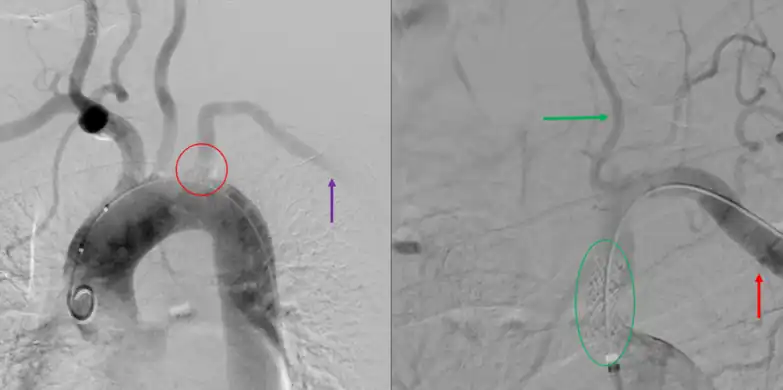

Restoration of flow in the left subclavian artery across a propaten graft from the right subclavian artery.

Angiogram of subclavian steal phenomenon before and after stent placement